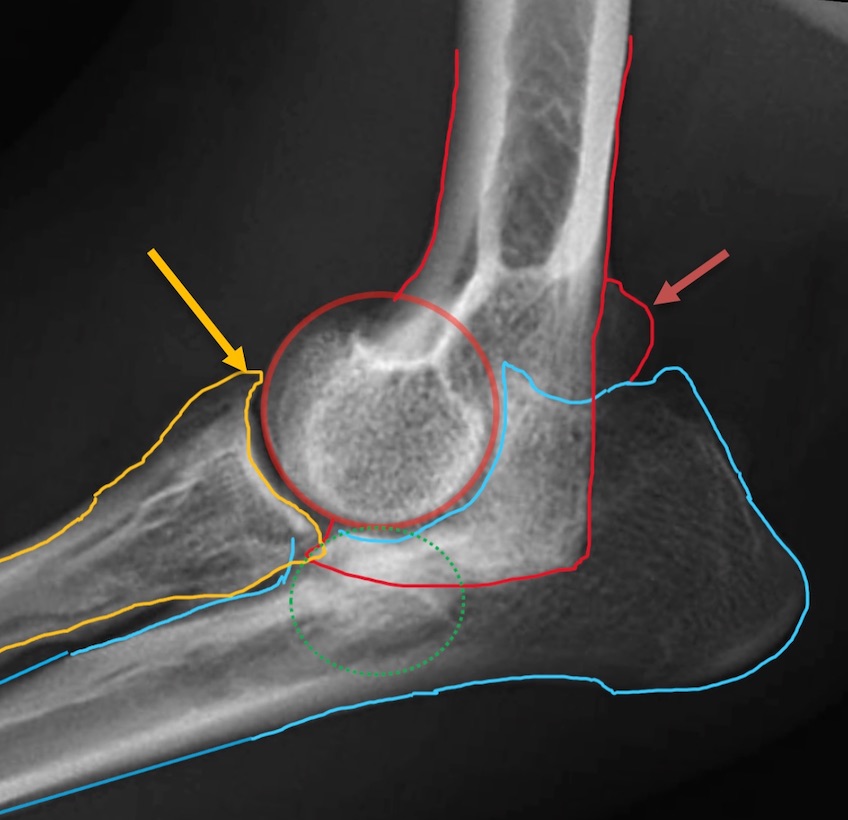

整形外科

本コラムでは獣医療の専門的な情報を取り扱っており、手術中の写真など刺激を受ける可能性のある医療画像を含む場合があります。